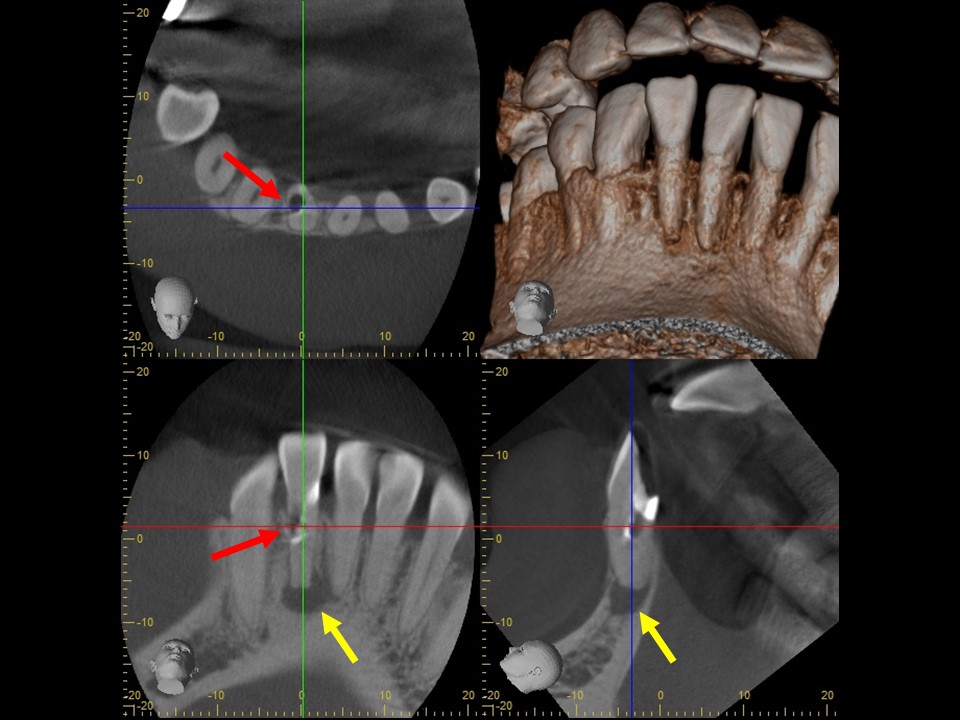

当該歯のレントゲンおよびCTによる診査にて、根尖部に根尖病巣と思われるX線透過像を認めました。また、歯根の側方には歯の方向を間違えて削った跡があり、パーフォレーション(穿孔、穴)が疑われました(下写真)。

歯髄壊死・歯髄壊疽から生じた慢性化膿性根尖性歯周炎と診断し、感染根管治療を行うことにしました。

パーフォレーションがある場合は、バイオセラミックセメント(MTA,RRMなど)でリペアをする計画としました。

術前のレントゲンおよびCT画像です。根尖部に根尖病変と思われるX線透過像を認めます(黄矢印)。歯根の側方には、方向を間違えて削ったと思われる跡が見られます。

根管充填後のレントゲン画像です。パーフォレーション部にバイオセラミックセメントが充填されているのが分かります(赤矢印)。

根管治療7か月後のレントゲン画像です。根尖病変はきれいに治癒し、骨の再生を認めます(黄矢印)。パーフォレーション部も骨吸収は認めず、予後は非常に良好です。

根管充填3か月後のCT画像です。根尖病巣は顕著に縮小しており、骨の再生を認めます(赤矢印)。上顎洞の炎症も消退し、ほぼ正常像を呈していることが分かります(黄矢印)。病状が治癒傾向を認めるため、歯冠修復処置を行っていきます。

根管治療14か月後のレントゲンおよびCT画像です。術前にあった根尖部のX線透過像(赤矢印)ならびに上顎洞内のX線不透過性の亢進(黄矢印)は完全に消失し、根尖病変および歯性上顎洞炎は良好に治癒しているのが確認できます。